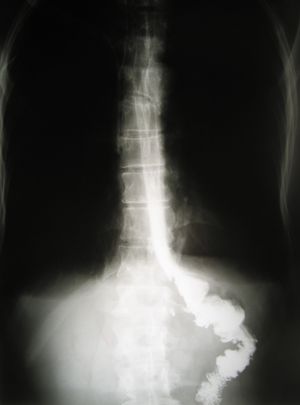

Рентгенограмма пищеводнокишечного анастомоза